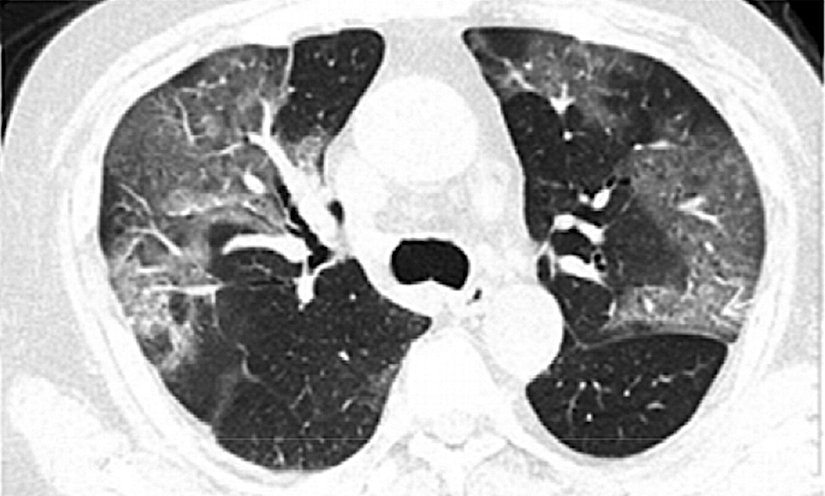

Yeni teşhis yöntemi ise bilgisayarlı tomografi (CT, Computed tomography) yöntemi. Bu yöntemle, hastaların akciğerleri taranıyor ve enfekte olmuş hastalar kolayca tanımlanabiliyor. Göğüs taraması COVID-19’un belirgin pnömoni (zatürre) paternini ortaya çıkarıyor. Bu yöntem ile yetkililerin hastaları daha çabuk izole etmesine ve tedavi etmesine olanak sağlayacağı düşünülüyor.

Üçüncü aşamada, akciğer hasarı oluşmaya devam ediyor ve solunum hasarı ile sonuçlanabiliyor. Ölüm gerçekleşmese bile, bazı hastalar kalıcı akciğer hasarı ile hayatta kalıyor. Dünya Sağlık Örgütü'ne göre, SARS akciğerlerde delik açarak “petek benzeri bir görünüm” oluşturuyor ve bu lezyonlar yeni koronavirüsten etkilenenlerde de var.

Bu durumda, hastalar nefes almaları için sıklıkla ventilatörlere bağlanıyor. Bu arada iltihaplanma, hava keseleri ve kan damarları arasındaki zarları daha geçirgen hale getiriyor ve bu da akciğerleri sıvı ile doldurarak nefes alımını etkileyip ve ölüme yol açıyor.